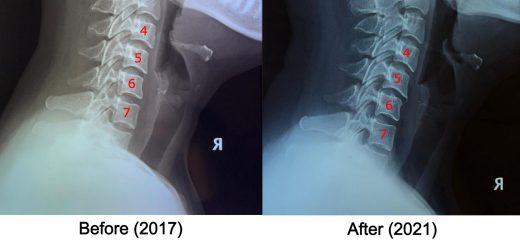

Reversal of L5 and L4 Disc Degeneration